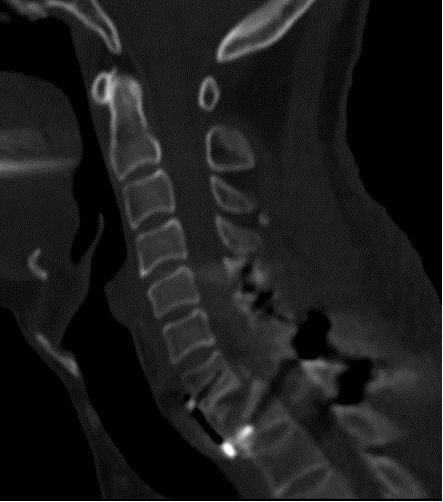

术前MR提示:C7椎体完全脱位,颈胸椎多发骨折

术前颈椎CT